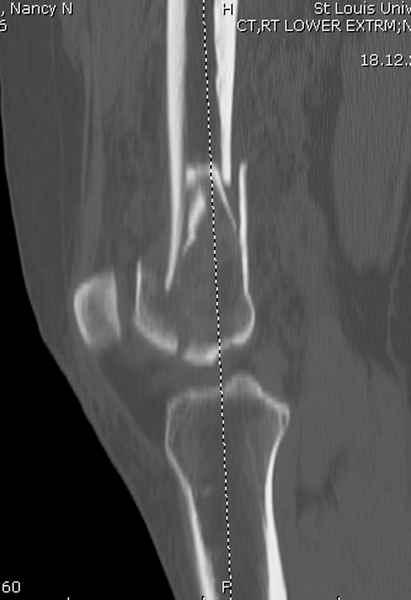

Приветствую всех коллег!!Во первых слева хотелось бы видеть четкую боковую проекцию а лучше КТ. По р-мам есть сомнения насчет повреждения суставной поверхности. При подобных переломах даже внутрисуставных без смещения хорошие результаты показал закрытый ретроградный остеосинтез универсальным бедренным стержнем Деост.Кстати при внутрисуставном переломе возможно применение вместо винтов стягивающих болтов!!(См. метод.Деост).При переломе справа также стержень Деост. Однако без открытия Вам не удастся устранить интерпозицию, только промучаетесь!Из минимального разреза удалите интерпозициб и фиксируйте стержнем. Причем универсальный стежень Деост позволяет фиксировать дистально минимум на трех уровнях!

Мы бы не стали открывать, такие переломы срастаются, хотя бы и с краевым дефектом. То есть если удалять стержень потом, то сильно попозже обычного. В приложении пример. Сразу после операции и через 11 мес. Понятное дело, пациент к тому времени давно и не хромал, и функция колена была полная.

Уважаемые коллеги! От имени Алексея Смирнова всем спасибо за обсуждение. Больной прооперирован. Снимки в приложении.